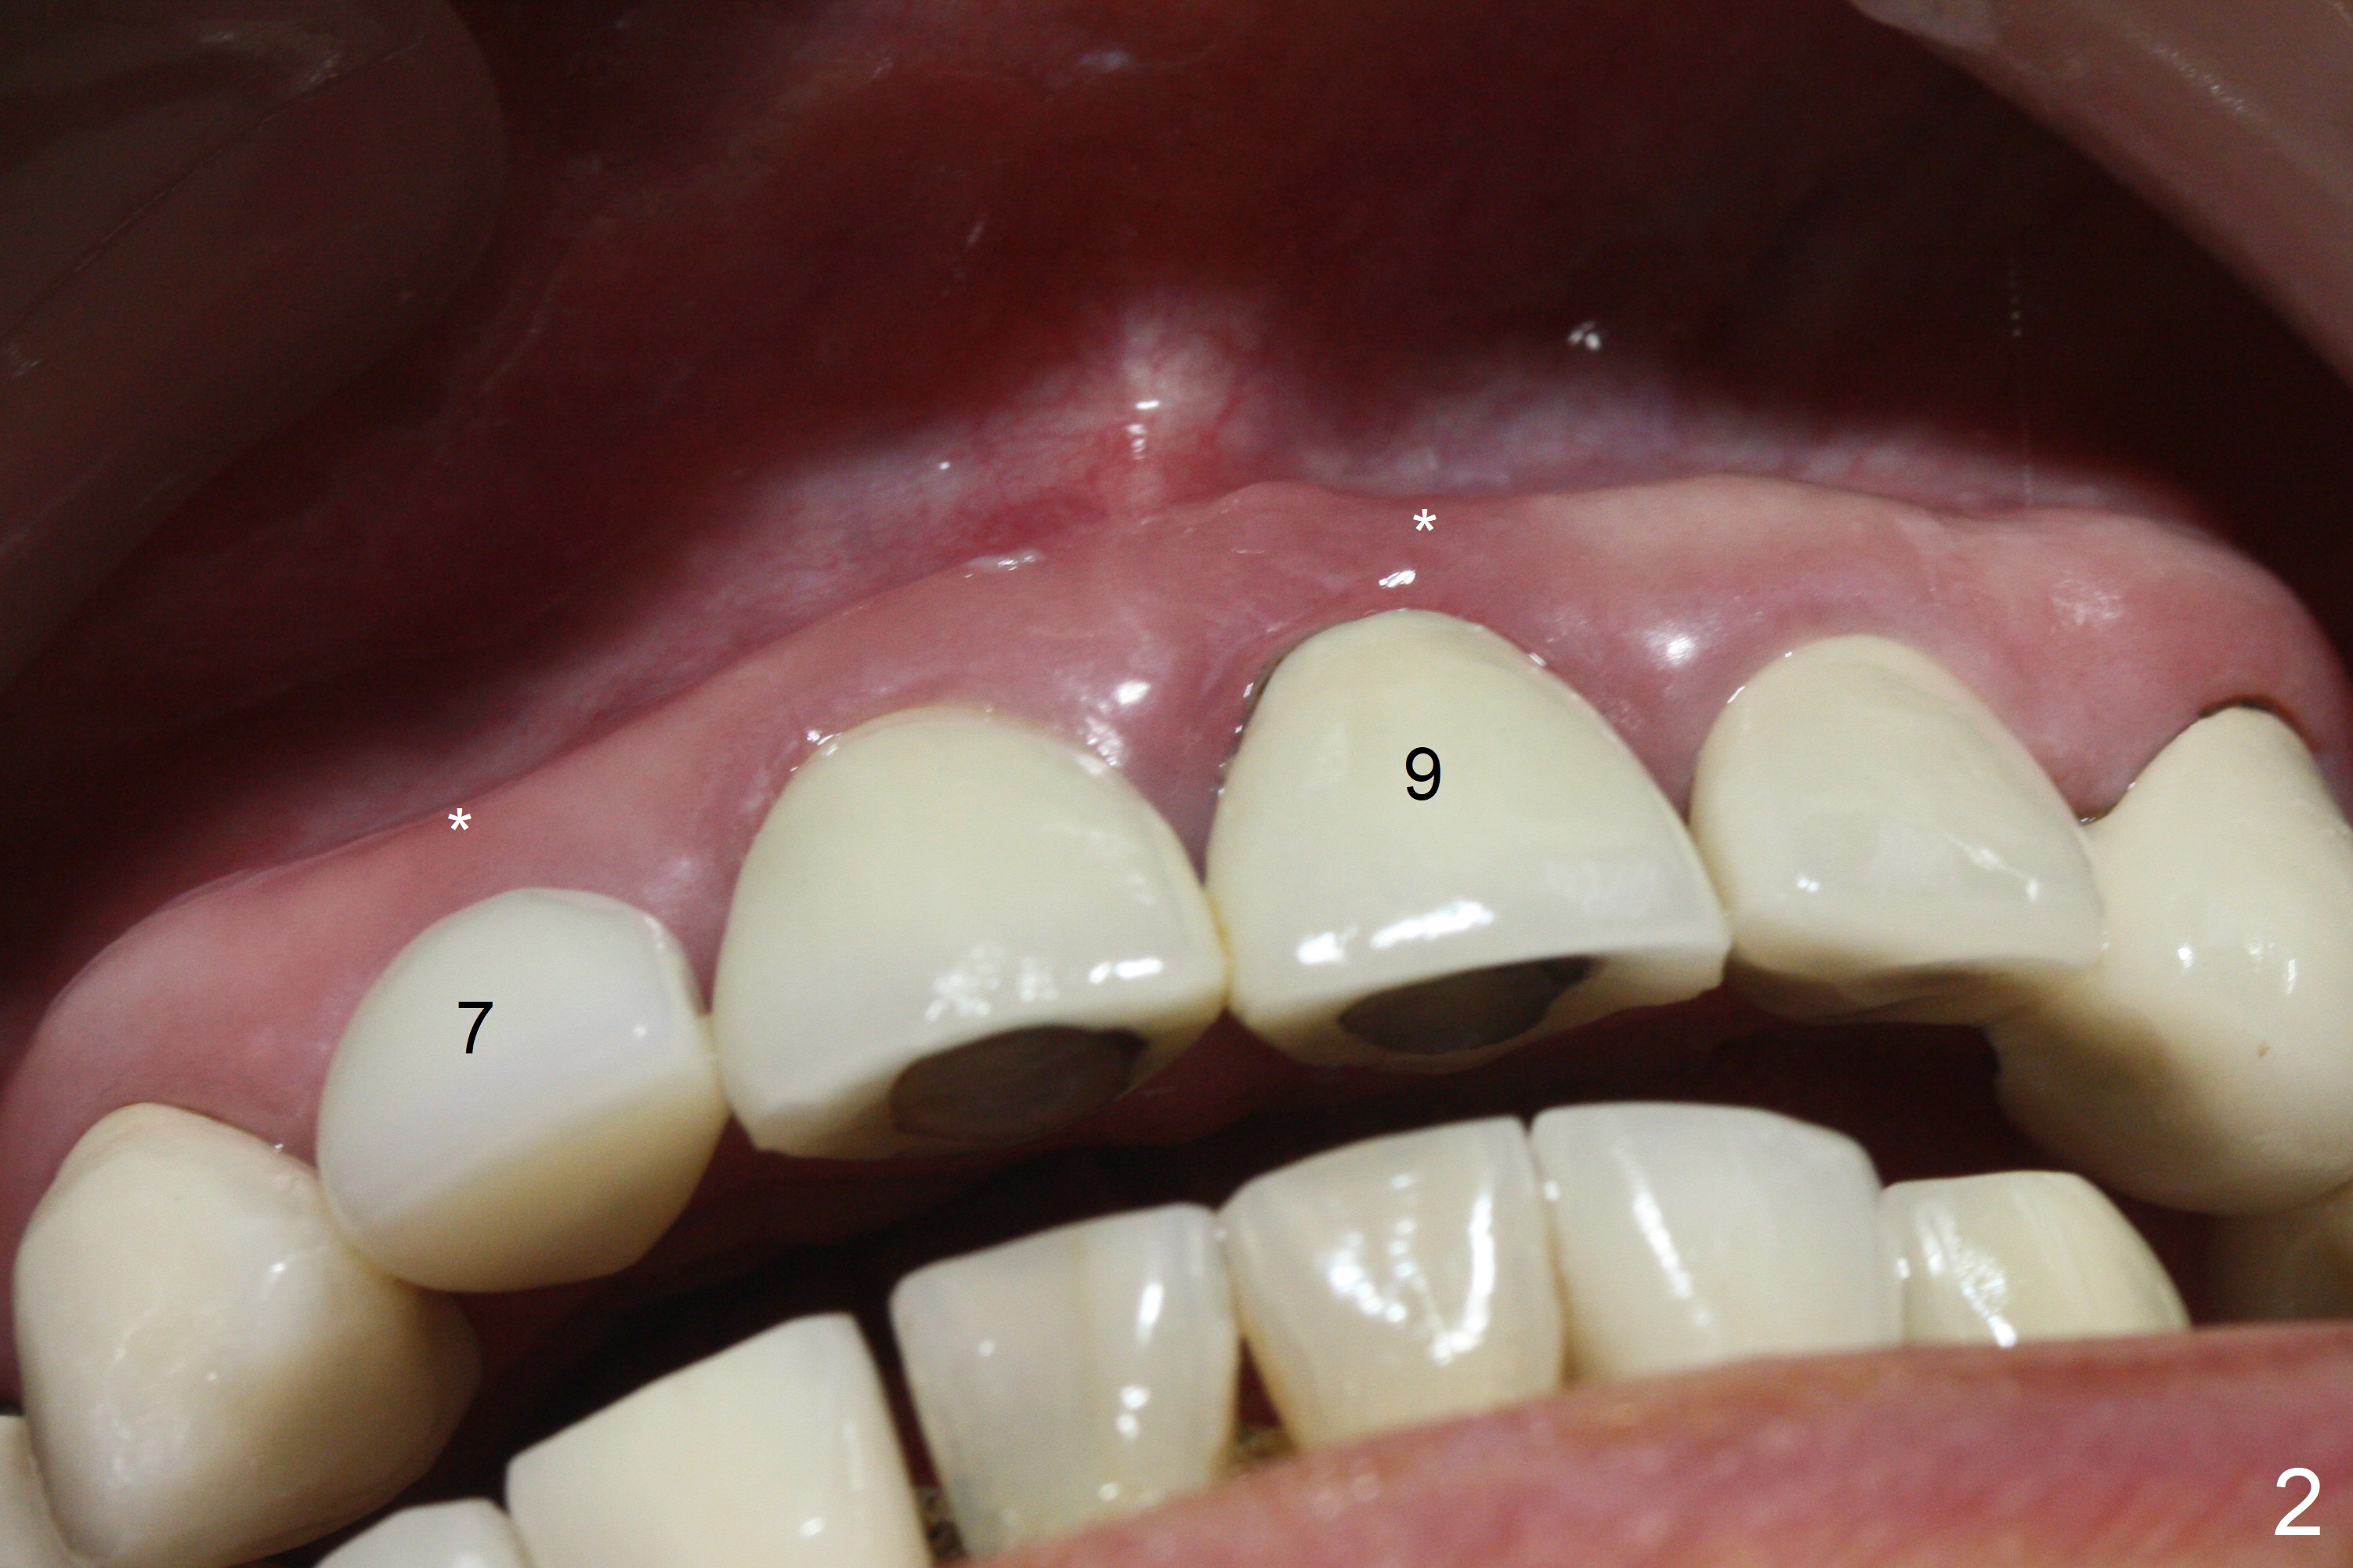

Nasal Floor

The buccal contour at #9 seems to be slightly concave preop (Fig.1,2 (*)). In fact the buccal plate is found to be lost when the tooth is extracted. Osteotomy is initiated as palatal as possible apical, but the occlusion dictates the coronal end of the osteotomy should be buccal, leaving the buccal gap ~ 2 mm for bone graft. The initial osteotomy (18 mm deep) appears to be close to the Incisive Foramen (Fig.3 blue dashed line). The nasal floor appears to be intact when the drill is removed. Subsequent osteotomy is adjusted so that the apical end of the osteotomy moves distal; when a 3.8x15 mm dummy implant is partially placed, there is clearance (Fig.4). It remains so when a definitive implant is seated (Fig.5); Vanilla graft is placed (Fig.5 *) before placement of a 4.5x5.5(3) mm abutment. More allograft is placed when an immediate provisional is fabricated (Fig.6 arrow and *). The gingiva remains to be recessive 1 month postop (Fig.7). It seems to be related to the bulky gingival margin of the provisional (Fig.8 *). After trimming the latter (Fig.9 *), the gingival margin immediately returns close to normal (Fig.10). The gingival margin is even between #8 and 9 two months postop, but the bone graft is exposed apically (Fig.11 ^). It may heals by itself. Otherwise debridement, regraft, PRF and suture are pending. The coronal portion of the socket heals 4 months postop (Fig.12). The gingival cuff forms by the immediate provisional (which is removed for impression) 4 months postop (Fig.13 *). While the full Zirconia crown at #7 remains intact (Fig.14), the PFM at #9 has porcelain chip (Fig.15). It is partially due to the occlusion; while the crown at #7 has clearance with the opposing dentition (Fig.16 *), the one at #9 has no. The access hole at #9 (Fig.17 *) seems to weaken the crown structure. There is no access hole at #7. No solid posterior support is another contributing factor for chip (Fig.18). The buccal plate has mild atrophy at #7 and 9 (Fig.19 *). A piece of bone graft is being expelled apically at #9 (Fig.20 >) and is removed subsequently (Fig.21). Before impression for repacking porcelain, the opposing incisal edge has been shortened (Fig.22 arrows, as compared to Fig.16). Since the ideal access hole is at the incisal edge (Fig.25 black circle), buccal to the existing one (Fig.24 A), the abutment is torqued before the repaired crown is recemented (Fig.23). Finally the crown has occlusal clearance (Fig.26). Porcelain chips again around the access hole of PFM 1.5 years post 2nd cementation. The dense bone at the crest (*) cannot explain why the abutment is not loose, since it remains incompletely seated (>). As it was trimmed short, an angled abutment is used (Fig.28). The coronal end is lingual, while #9/24 is edge to edge. The lingual aspect of the coronal end of the abutment is heavily trimmed to reduce bulkiness. To prevent chip, Zirconium crown will be fabricated in spite of the fact that it does not match the PFM of #8 (potential shade discrepancy). The patient is pleased with the new Zirconia crown (Fig.29).